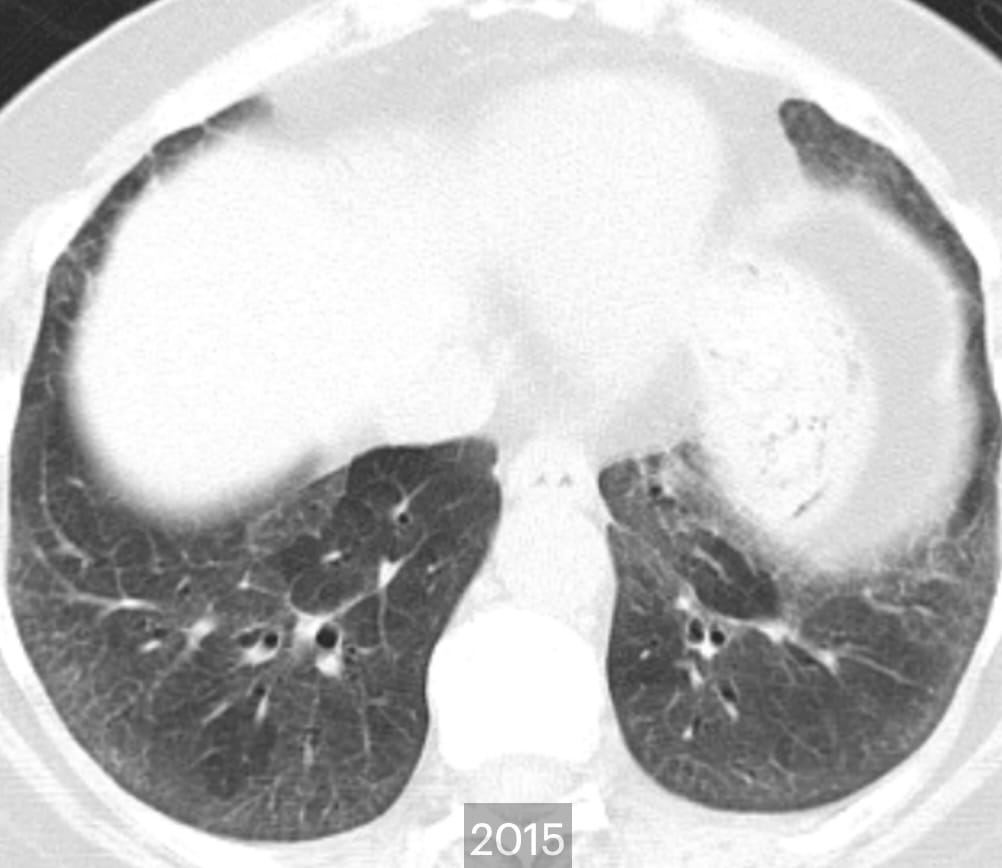

- Fibrotic Hypersensitivity Pneumonitis